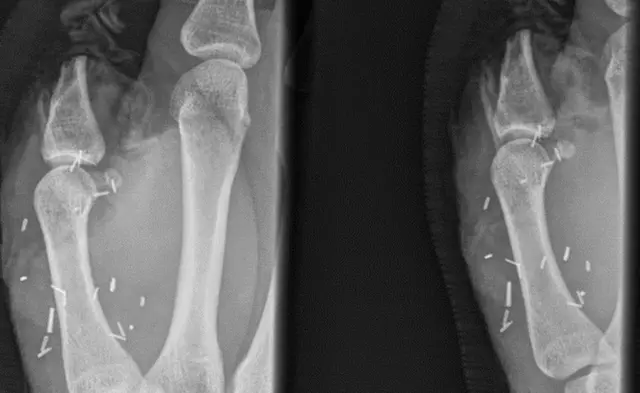

زرع جراحون أصبع قدم في مكان الإبهام لمواطن أسترالي يعمل في تربية الماشية، بعد أن قُطع إبهامه في هجوم ثور.

وخضع ميتشل لعميلتين جراحيتين لم تنجحا في إعادة إلصاق أصبع الإبهام، قبل أن يلجأ الأطباء لنقل أصبع قدمه الكبير ووضعه مكان الإبهام في جراحة استغرقت ثماني ساعات.

ورغم رفض ميتشل في بداية الأمر، وافق مربي الماشية على إجراء عملية الزرع في مستشفى العيون في سيدني قبل أسبوعين.

وقالت مستشفى العيون في سيدني إنه من النادر زراعة أصبع قدم كامل كما في حالة ميتشل، لكن من الشائع إجراء جراحات لزرع أجزاء من أصابع القدم في أماكن أخرى.